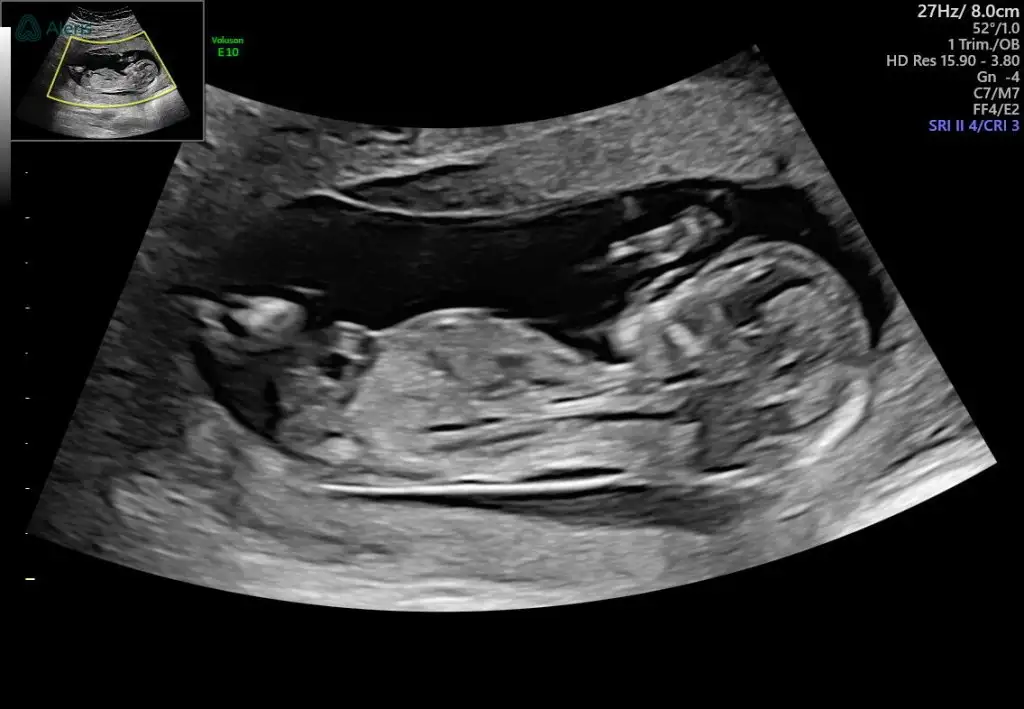

Merhaba kızlar bugün 12+6 olduk bizim minik inatla göstermedi cinsiyetini sonda da iki eliyle bacak arasını kapattı resmen bir sonra ki kontrolüme daha çok var meraktan çatlicam resmen tahminlerinizi alabilir miyim lütfen 😀🌸

Cinsiyeti anlayabiliyor musunuz? Kızımda fetal dna yaptırmıştık. O yüzden cinsiyeti kesindi. Burada henüz karar veremedik. Merak ediyorumm tahmin edebilir misiniz?